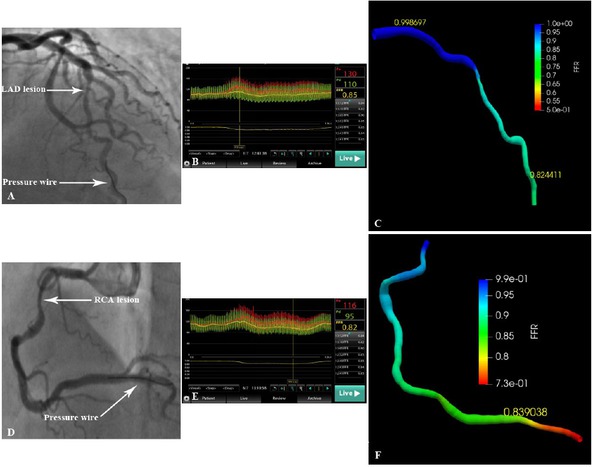

As a data-driven model, the deep learning algorithm represents a new concept in the field of artificial intelligence. They are based on neural networks to simulate the human brain for the analysis of a large amount of data.[38] Compared to traditional methods, the deep learning algorithm is more efficient and time-saving.[39, 40, 41] The basic principle of FFRCT-angio is to directly learn the anatomical structure and functional information from images to derive the hemodynamic relevance of blood vessels. With increasing data volume, this data-driven approach can further improve its performance. By contrast, FFRCT and QFR are model-based approaches, and their performance will generally not improve as the data size increases. Additionally, the diagnostic performance of FFRCT-angio is not affected by severe calcification because only the centerline is extracted from CCTA images. More importantly, in this approach, only one angiographic projection with clear vascular contour is required for the 3D reconstruction, and it can complete the vessel reconstruction of tortuous lesions unsuitable for QFR measurements, thus expanding its clinical applications. For example, 5 of 67 target vessels in this study failed in the 3D reconstruction based on the 2D angiographic image due to obvious tortuosity or vessel overlap. With the integration of CCTA and CAG data, the 3D images of these five vessels were accurately reconstructed, and the FFRCT-angio value was subsequently calculated (Figure 6). As for the clinical use of FFRCT-angio, it should be applied to patients for which both CCTA and CAG data exist. CCTA has been recommended by guidelines in patients with stable CAD as the initial screening modality. If an ischemia-causing lesion was found, CAG would be needed to further clarify the severity of the stenosis. For such patients, CCTA and CAG images can be integrated to functionally assess the lesion by FFRCT-angio, thereby avoiding subsequent invasive FFR measurements.

Reconstruction and hemodynamic assessment of coronary arteries with severe overlap or tortuosity by FFRCT-angio. (A) Inability to reconstruct the LAD using angiographic images due to severe vessel overlap. (B) The FFR value measured using the pressure wire was 0.85. (C) Successful reconstruction of the LAD and subsequent FFR calculation using the integration of CCTA and CAG images (FFRCT-angio = 0.82). (D) Inability to reconstruct the RCA using angiographic images due to severe tortuosity. (E) The FFR value measured using the pressure wire was 0.82. (F) Successful reconstruction of the RCA and subsequent FFR calculation using the integration of CCTA and CAG images (FFRCT-angio = 0.84). CAG: coronary angiography; CCTA: coronary CT angiography; FFR: fractional flow reserve; LAD: left anterior descending artery; FFRCT-angio: fractional flow reserve derived from integrated CT angiography and invasive angiography; RCA: right coronary artery.